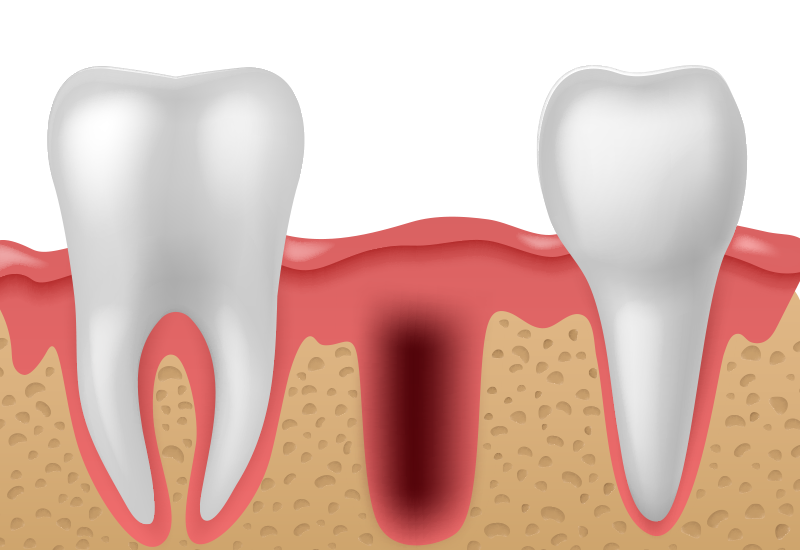

치아 상실 후 오랜기간이 지나 잇몸뼈가 많이 흡수된 경우 치조골 이식술을 동반하여 임플란트를 시술하게 됩니다. 치조골을 형성하는 단백질로 이루어진 뼈이식재는 뼈 조직내의 줄기세포를 자극하여 잇몸뼈를 빠르게 회복시키는 것을 도와줍니다.

틀니의 오랜 사용, 만성 치주염, 충치 등으로 치아가 소실되고 오래 방치되어 치조골이 녹아 내린 경우 임플란트 시술이 어렵습니다.